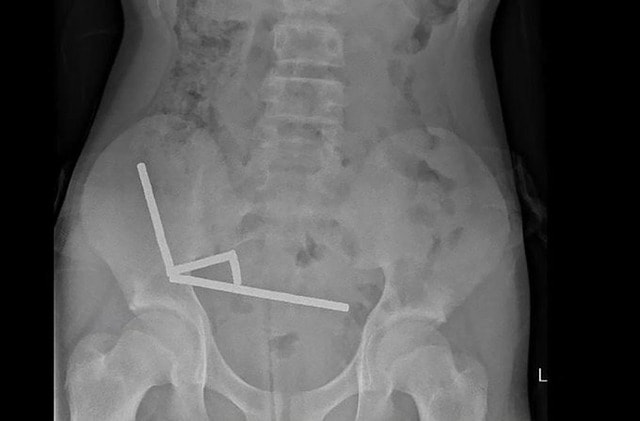

Trong một vụ việc gây sốc ở New Zealand, cậu bé 13 tuổi đã phải trải qua một cuộc phẫu thuật khó khăn sau khi nuốt phải hàng chục viên nam châm mua từ một trang thương mại điện tử trên Internet. Các bác sĩ đã phải cắt bỏ một phần ruột của cậu bé để lấy ra toàn bộ số nam châm.

Các bác sĩ phẫu thuật tại Bệnh viện Tauranga đã viết trên Tạp chí Y khoa New Zealand rằng cậu bé tuổi teen đã nuốt khoảng 80 đến 100 viên nam châm nhỏ một tuần trước ca phẫu thuật. Cậu bé đã mua chúng ở Temu.

Cậu bé tiết lộ đã nuốt khoảng 80–100 80–100 nam châm (neodymium) loại mạnh, kích thước 5x2mm khoảng một tuần trước đó, được mua từ một chợ trực tuyến ở nước ngoài (Temu)".